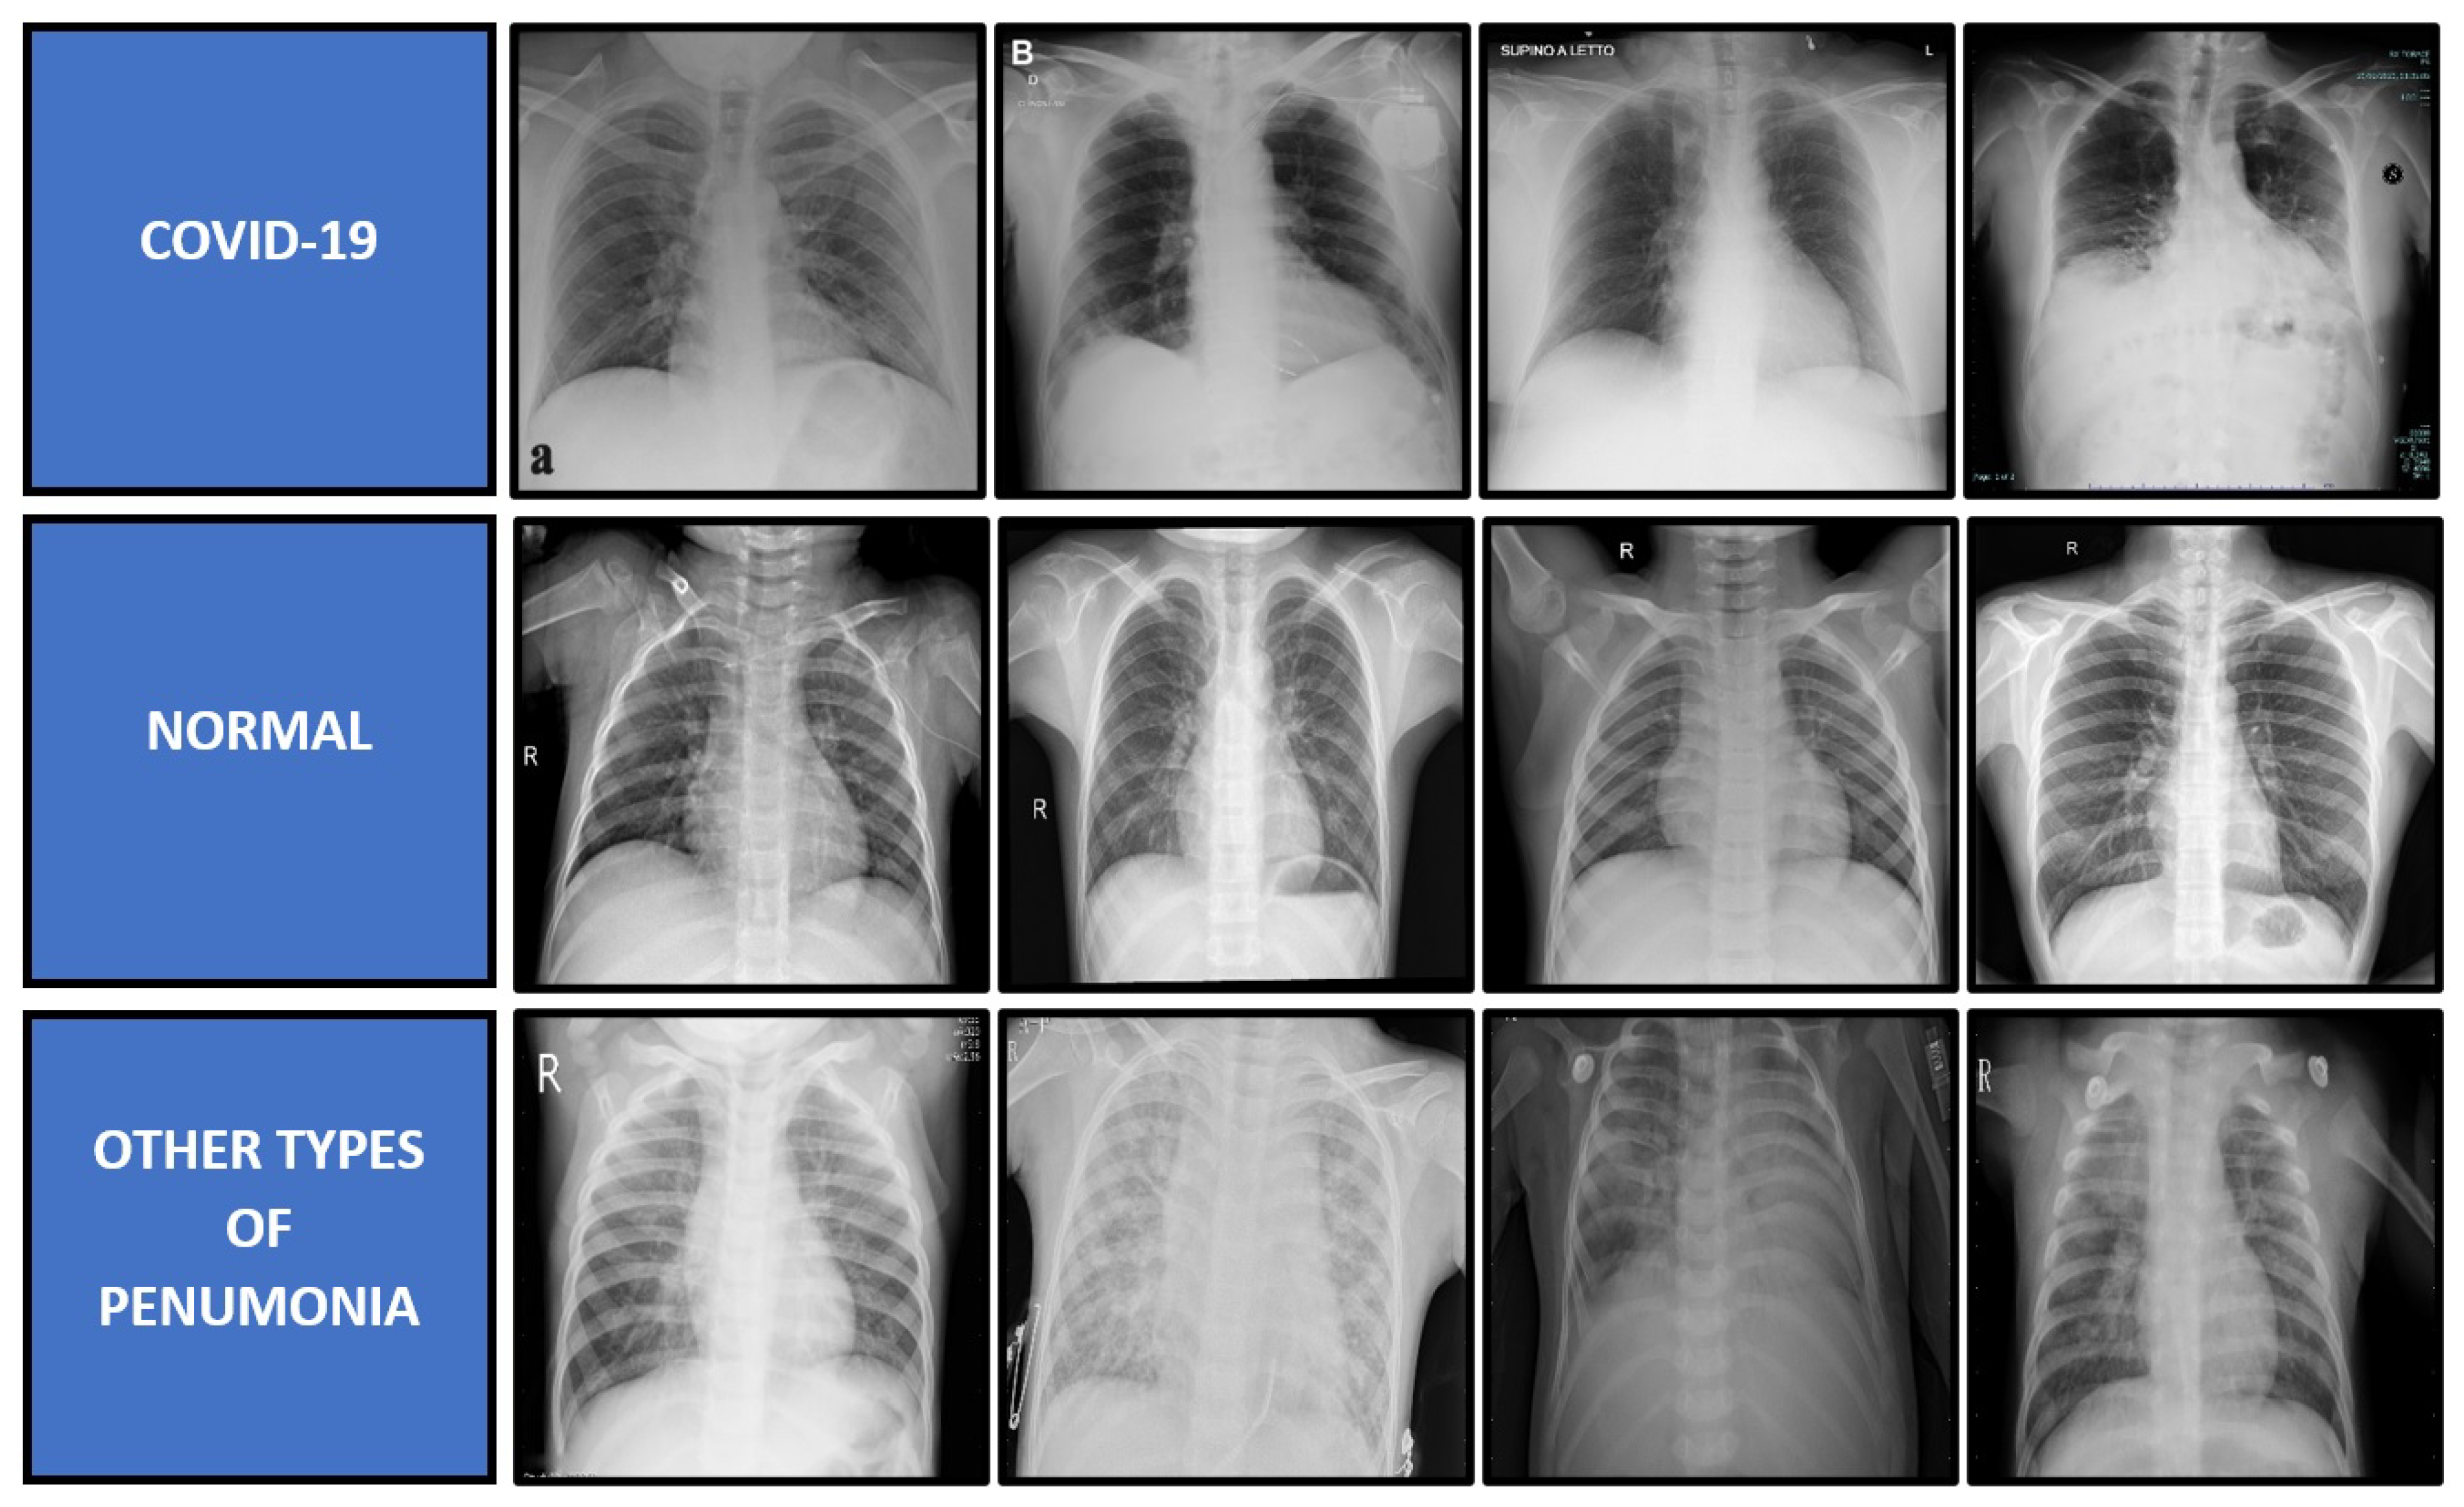

4.1. Dataset